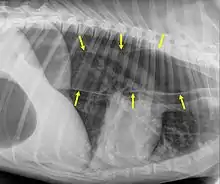

Megaesófago, también conocido como dilatación esofágica, es un trastorno del esófago en humanos y otros mamíferos, donde el esófago se agranda de forma anormal. El megaesófago puede ser causado por cualquier enfermedad que haga que los músculos del esófago no puedan impulsar adecuadamente los alimentos y el líquido de la boca al estómago (es decir, una falla de la peristalsis). Los alimentos se pueden alojar en el esófago flácido, donde pueden descomponerse, regurgitarse o inhalarse en los pulmones (lo que conduce a una neumonía por aspiración).

El megaesófago puede aparecer como consecuencia de enfermedades como la acalasia o la enfermedad de Chagas. La acalasia es causada por una pérdida de células ganglionares en el plexo mientérico. Existe una marcada falta de contracción dentro de los músculos involucrados en la peristalsis con una contracción constante del esfínter esofágico inferior. La dilatación del esófago resulta en una dificultad para tragar. También se observa la retención del bolo alimenticio .